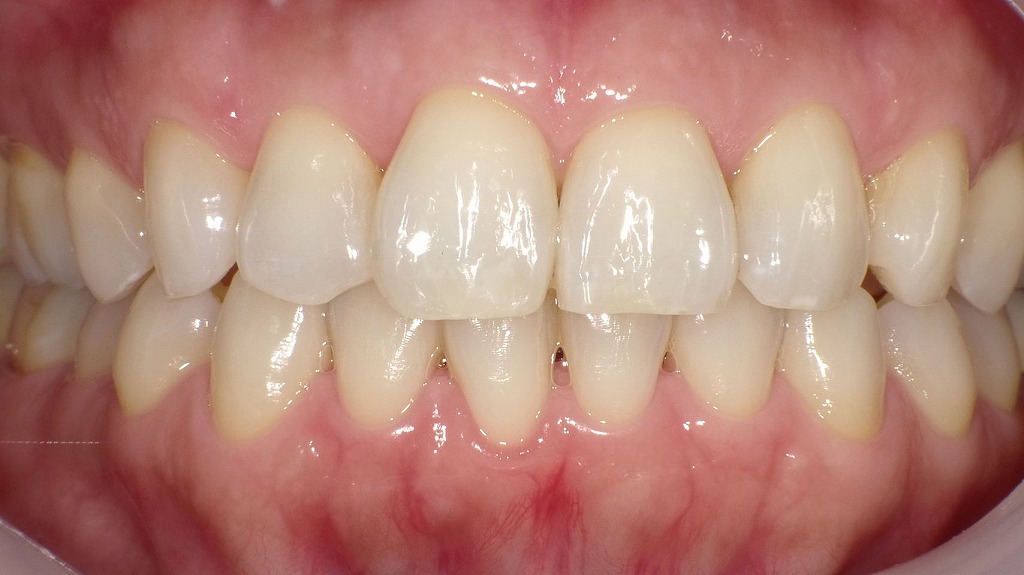

- 1.3.2. 2枚目の画像:ホワイトニング後

2枚目の画像:ホワイトニング後

2枚目の画像では、ホワイトニング後の状態を示しています。歯全体が明るくトーンアップしており、周囲の色とのコントラストが減少したことで、ホワイトスポットがほとんど目立たなくなっています。ホワイトニングによって歯全体の明度が上がることで、白斑が自然に馴染み、全体として均一な印象に改善されています。

このように、ホワイトスポット自体を「消す」ことはできませんが、ホワイトニングで目立たなくすることは可能です。